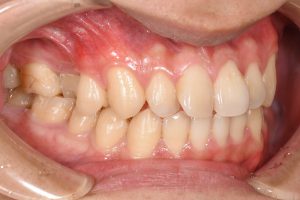

銀歯を全てセラミックにした症例

完成したセラミックインレー

治療後

この患者様の場合

1回目にカウンセリング

2回目に型取り

3回目にセラミックのセット

の合計3回で治療終了となりました。